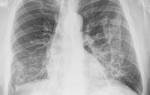

При рентгенологическом исследовании брюшной полости могут выявляться увеличенные и измененные лимфатические узлы в виде овальных или округлых образований, часто зернистой структуры вследствие отложения в них извести (рис.53).